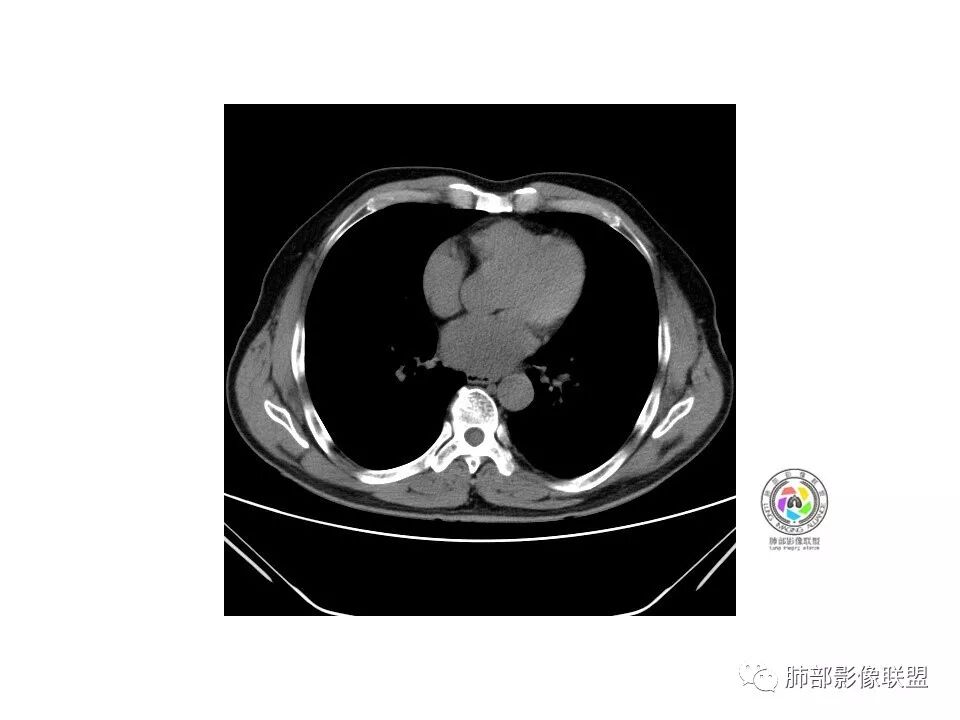

1.纵膈窗未显示;水平裂有轻微凹陷,那个条索影,有形成机理进一步分析;前方那个血管,可能是肺动脉?有一定弯曲度(向病灶),后方这个是肺静脉;3个小叶凹,有可能,受到阻挡,邻近小血管有相应改变;薄层那个细小血管有弯曲,形成部分实性;

2.大小:估计15*10mm左右;

3.CT值:混杂,有些偏高;

4.周围小血管,有形成毛刺趋势;

5.血管:如上述;

6.胸膜和叶间裂:有轻微牵拉;

诊断:浸润性腺癌;鉴别:炎性结节;

右肺下叶mGGN,内部结构紊乱,可见小点状高密度影,边缘清晰,小叶间隔阻挡,轻度收缩力,考虑MIA,常规飞一会20天复查。

老年男性,右肺下叶前基底段GGN,界清,内部血管结构杂乱,叶间胸膜牵拉。考虑恶性,早期腺癌可能,建议抗炎治疗后复查对比。

右肺下叶前基底段见一磨玻璃结节影,呈分叶状,边缘部分模糊,与胸膜间有长条索粘连,内有增粗的血管影,后者边缘毛糙,考虑微浸润性腺癌,建议抗炎治疗后复查

右肺下叶mGGO,边缘清晰,浅分叶,内血管影增粗,见点状实性成分,小支气管牵拉扩张,考虑MIA,建议抗炎后复查。